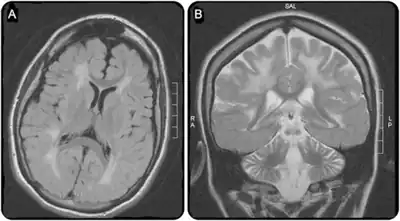

a)Extensive white matter disease b) atrophy of frontal hemispheres and cerebellum

Cerebral CT-scan at 4 years old. Red arrows show brain calcifications (A) and diffuse white matter abnormalities (B). From Mafi et al., 2020[15]